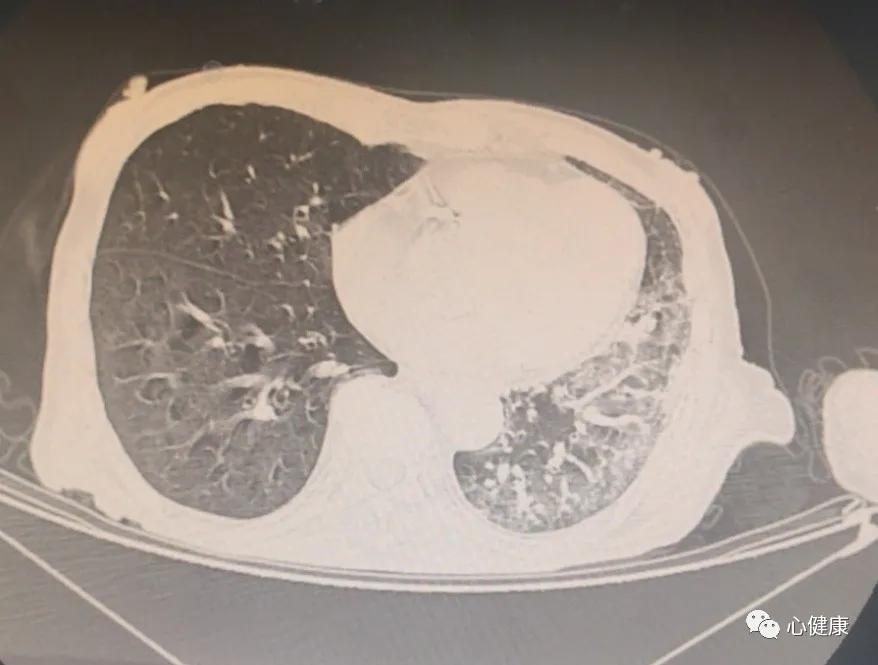

赶紧拉着做了一个胸部CT,这明显的就是一个吸入性肺炎啊!难道患者是因为吃饭呛着了?老年人,有过脑梗塞,这些都好解释,联系呼吸科,准备做个气管镜看看!